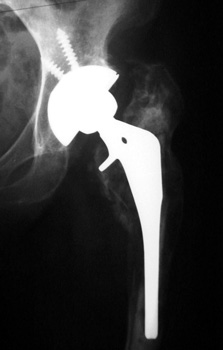

No prior studies available. Abnormally widened interfaces surrounding entire cement mantle of femoral component, consistent with loosening.

LOOSENING

No prior studies available. Abnormally widened interfaces about femoral component at Gruen zones 1, 6, and 7. Osteolysis at Gruen zone 5 with marked thinning of femoral cortex placing patient at risk for pathologic fracture.